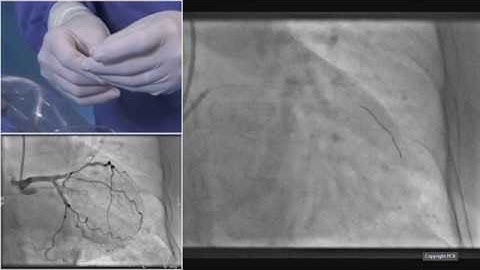

Imaging and functional guidance for left main and bifurcation PCI - Round Table Webinar